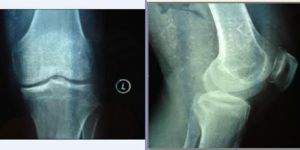

膝關節退行性變發病機理

膝關節退行性變又是怎樣發生的呢?正常的膝關表面有一層很薄但十分耐摩擦的透明軟骨,呈淺蘭色,半透明,光滑而有光澤。這層耐摩的透明軟骨在膝關節的運動功能中十分重要。膝關節在人體中屬負重最大和運動最多的關節,因而也是人體中退化最早、損傷最多的關節。45歲以上的中老年人,尤其是女性,由於其體內激素水平下降,會引起膝關節的透明軟骨退化、萎縮,再加上一些輕微的損傷,其光滑如鏡的透明軟骨便會出現點狀的“銹斑”,也即出現局部壞死。此時,身體會動

員個種內在力量來修復“銹斑”,包括滲出越來越多的關節液和骨質修復。但滲出的關節液為酸性液體,不僅不利於“銹斑”的修復,反而形成多種化學性炎症介質刺激源,引起關節周圍腫脹、疼痛、行走困難等一系列症狀。